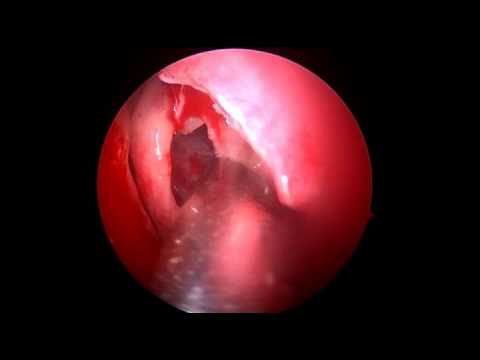

Edoskopowa septoplastyka: niewielka ostroga

Nagranie przedstawia endoskopową septoplastykę - usunięcie ostrogi przegrody nosowej po stronie lewej